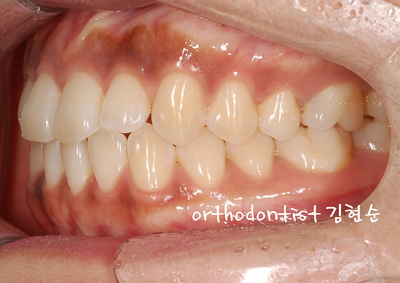

- 치아 사이사이 공간 벌어지고 치아 심선도 맞지 않습니다,

- 상 / 하 치아 벌어짐을 보실 수 있습니다 아래쪽이 더 벌어짐이 심해 보입니다

- 오른쪽 옆모습 벌어진 모습을 확인할 수 있습니다